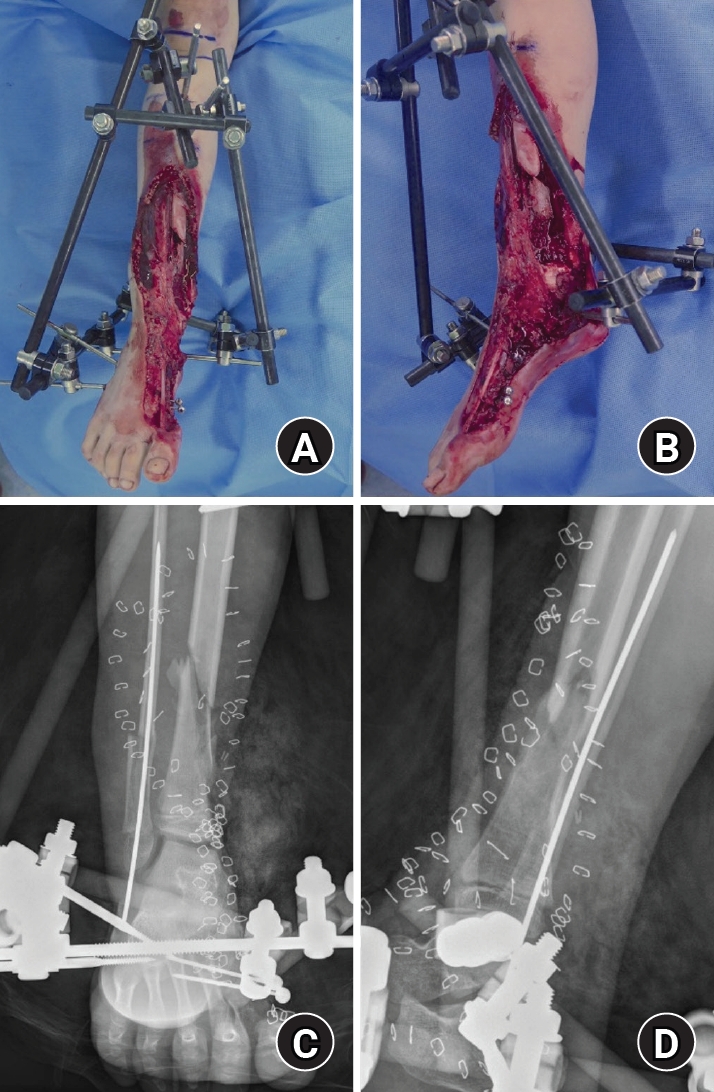

Stage 4 (alignment and contracture management; May 29, 2017)

The patient was observed for more than 6 months after plate fixation, and bone union was achieved for the remaining fracture sites. However, varus deformity gradually occurred (lateral distal tibial angle, 111.5º; tibiotalar tilt, 0.4º). As the patient was relatively young and had substantial remaining growth, early correction was considered advantageous and was therefore performed. Residual deformity tendency and contracture were managed with additional procedures including Achilles tendon lengthening and Z-plasty for tendon/skin contracture release. The bone-cement spacer was removed during this phase. Alignment correction/overcorrection and continued alignment management were supported with an Ilizarov external fixator (Fig. 7). After applying the Ilizarov external fixator for 3 months, radiologic indices were corrected (lateral distal tibial angle, 97.6º; tibiotalar tilt, 0.3º).

Fig. 7.

Ilizarov fixation for correction/overcorrection. (A) Anteroposterior radiograph obtained after application of an Ilizarov external fixator for deformity correction, intentional overcorrection, and alignment management. (B) Lateral radiograph obtained after application of an Ilizarov external fixator for deformity correction, intentional overcorrection, and alignment management.

Fig. 7. Ilizarov fixation for correction/overcorrection. (A) Anteroposterior radiograph obtained after application of an Ilizarov external fixator for deformity correction, intentional overcorrection, and alignment management. (B) Lateral radiograph obtained after application of an Ilizarov external fixator for deformity correction, intentional overcorrection, and alignment management.